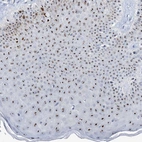

Immunohistochemical staining of human skin shows strong positivity in nucleoli in squamous epithelial cells.